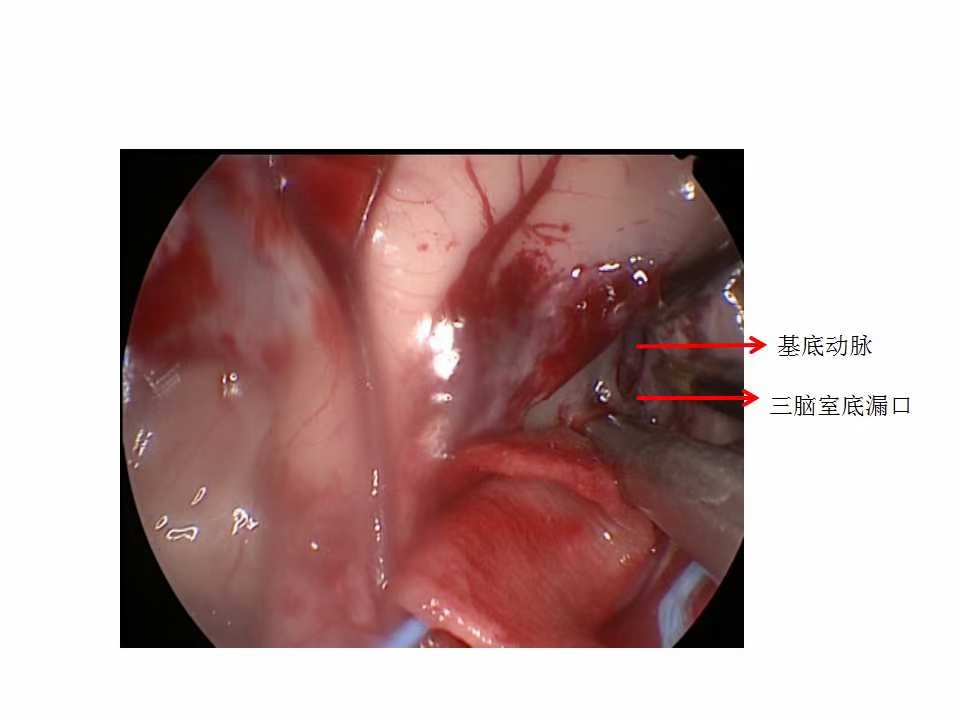

术中所见结构